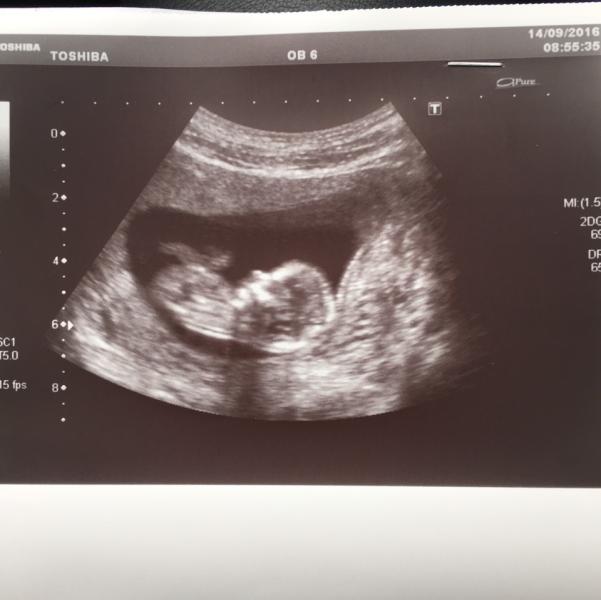

Первый скрининг был сегодня, кровь конечно не готова, но по узи тфу тфу, нос есть, даже какой то носище)), пальчиков по 5 ))) вообще все показатели в норме, соответствуем 12,2 нед

Предположили мальчика, но очень не точно, не показался да и не выросло пока)) какой то он гиперактивный по время узи был, крутился,переворачивался, руками ногами мешал, все ему мешало, еле словили его ))

У меня точно такая же ситуация, до мелочей;) писала пост тоже как то: срок поставили по первому скринингу 12.2, предположительно мальчик и тоже слишком активный;) сколько см сказали?

У нас не показался передом вообще, говорит промелькнуло что то похожее на мальчика но не будет предполагать сказала даже )) ждём,очень хочется узнать уже )

Сегодня тоже ходила на скрининг, у моего нос еще больше😄